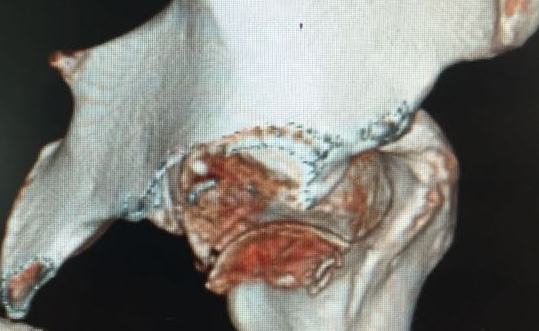

Мужчина, 50 лет, активный, падение с высоты. При поступлении вправление вывиха, других повреждений нет Без значимой сопутствующей патологии, не курит. Стоило ли выполнять остеосинтез при таком оскольчатом переломе или сразу пойти на ТНА?

На снимке №2 есть перелом заднего края суставной впадины,его, я так понял, решили не фиксировать? Фрагмент не очень большой.